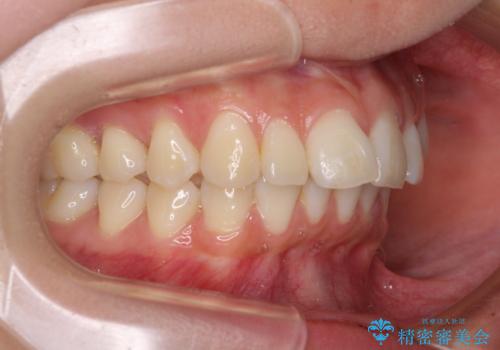

- 口を閉じたときに唇の間から飛び出してくる前歯を気にして来院された患者様です。

骨格的に上顎骨が前方位にあるため、左右の第一小臼歯を抜歯し、ワイヤー装置にて咬み合わせを整えていくこととしました。

前歯の突出感が改善されるだけでなく、奥歯の咬み合わせも改善され、食いしばりをしにくい状態に仕上げることができました。